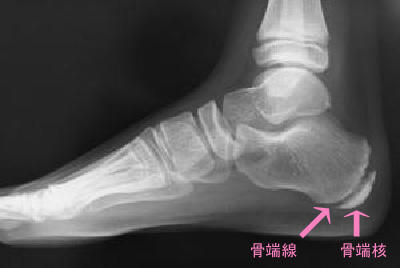

こどもの骨は骨端線・骨端核と言われる、成長軟骨部分が多数あり、

写真のように踵骨という、かかとの骨にも豊富です。

骨端部分は柔らかく、そこにアキレス腱や足底筋膜が付着します。